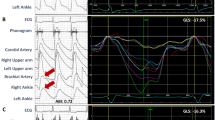

Slow varying components (0–0.05 Hz) in ECG and PPG signals were initially removed. ECG R-wave peaks were detected by a template-matching procedure28. With the location of R-wave peaks, the corresponding systolic feet were detected from the first-order differential signal of PPG29. PWTT series were constructed using the means of all intervals from the R-wave peaks to the feet of the corresponding PPG pulses in the same heart cycle3,30. Figure 3 demonstrates the construction process of PWTT time series from the synchronously recorded ECG and PPG signals. Anomalous intervals due to ectopic beats or poor signal quality were visually identified and removed from the PWTT time series.

” denotes the R-wave peak and “

” denotes the R-wave peak and “ ” denotes the foot of PPG. PWTT is defined as the interval from the R-wave peak to the foot of PPG signal in the same heart cycle.

” denotes the foot of PPG. PWTT is defined as the interval from the R-wave peak to the foot of PPG signal in the same heart cycle.